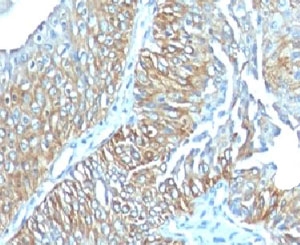

TRIM29 Antibody Mouse Monoclonal Lung Squamous Cell Carcinoma IHC. Immunohistochemistry of TRIM29 antibody mouse monoclonal TRIM29/1041 in human lung squamous cell carcinoma. Formalin-fixed, paraffin-embedded human lung tumor tissue shows HRP-DAB brown chromogenic signal with cytoplasmic and nuclear staining in malignant squamous epithelial cells, while surrounding stromal elements demonstrate minimal staining.